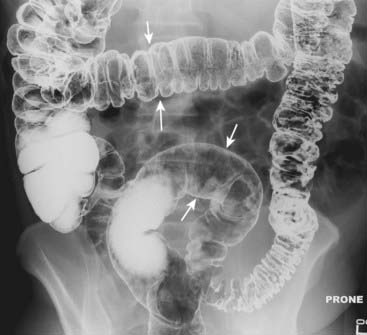

Figure 13-3 Normal colonic distension.

The colon can normally distend to the size of the diameter of the colon as seen on a barium enema (solid white arrows). Beyond this size, the colon would be considered dilated. This patient has had a double-contrast barium enema examination in which both air and barium are instilled as contrast agents. The combination allows for excellent visualization of the mucosal surface of the colon.